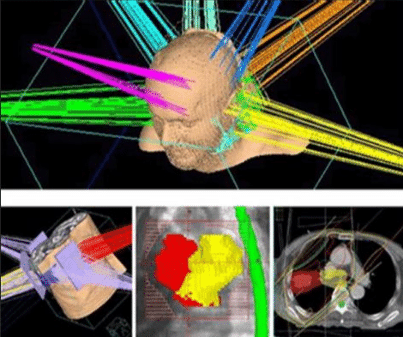

三維適形放療(3DCRT)

利用多葉光柵或適形擋鉛技術(shù),將照射野的形狀由普通放療的方形或矩形調(diào)整為腫瘤的形狀,從而使照射的高劑量區(qū)在人體內(nèi)的三維立體空間上與腫瘤的實(shí)際形狀相一致。三維適形放療提高了腫瘤的照射劑量,保護(hù)了腫瘤周圍的正常組織,降低了放射性并發(fā)癥,提高腫瘤的控制率。

與常規(guī)放療相比,3DCRT對腫瘤組織的適形聚焦照射和對正常組織的良好保護(hù),提高了腫瘤與正常組織的計(jì)量比。在正常組織受到允許劑量照射的情況下,腫瘤組織可以得到比常規(guī)放療更高的總劑量。治療時(shí)可以明顯地提高單次劑量,縮短總的治療時(shí)間??梢愿行У乇Wo(hù)正常組織,降低放射損傷,提高腫瘤的局部控制率。

適形放療是根據(jù)腫瘤的立體大小,從三維方向上,采用多野、多角度進(jìn)行照射,而且每個(gè)照射野的截面形狀與對應(yīng)的腫瘤形狀相一致。靶區(qū)形狀雖已適形,但靶區(qū)內(nèi)劑量分布欠均勻。